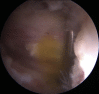

Acetabular labral tears are a known cause of hip pain in the young, active patient. Labral tears can be due to trauma, femoroacetabular impingement, capsular laxity, dysplasia, and degenerative pathology. Paralabral cysts are relatively common in association with labral tears of the hip, with cysts seen on magnetic resonance imaging studies in as many as 50% to 70% of patients with labral tears. In some cases the cysts can become sizeable and cause neurovascular compression. Nonoperative interventions for the management of paralabral cysts in the shoulder and knee have shown high recurrence rates. In the shoulder and knee, arthroscopic debridement of paralabral cysts has shown good results with lower recurrence rates and resolution of neurovascular function. In the hip there is limited literature regarding surgical management of paralabral cysts. We present a surgical technique for arthroscopic decompression of acetabular paralabral cysts combined with labral repair.